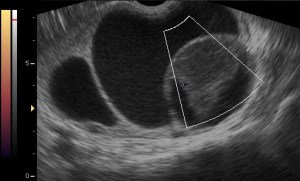

Ovarian Torsion 3